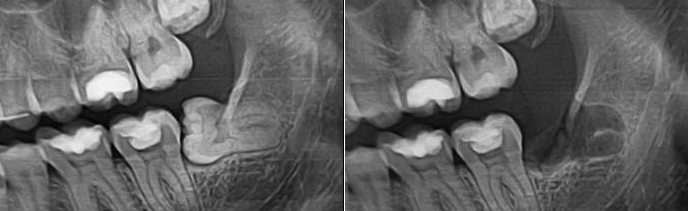

Сложное удаление зуба мудрости: фото до и после

Сложное удаление зуба предваряется проведением качественного рентгеновского обследования, поскольку восьмерка часто имеет искривленные корни, которые могут создавать трудности во время операции. Кроме того, ее корни часто становятся очагом воспаления, если при экстракции зуба загнутые кончики отламываются и остаются в толще кости.

Рентгеновский снимок перед процедурой сложного удаления зуба мудрости позволяет увидеть количество и строение корней восьмерки. Это гарантирует, что при поочередном извлечении частей зуба в кости не останется корней или их обломков.